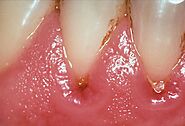

When periodontal (gum) disease develops, bacteria in plaque accumulate along the gum line. Gingivitis is the first stage of gum disease. Symptoms include red, puffy, and bleeding gums. Proper oral hygiene can help prevent periodontal disease. Smoking, poor diet, and stress can make it worse.

https://www.umbrellamd.com/e-visit

The next stage of gum disease is periodontitis, or gum infection. Increased inflammation causes the gums to recede, forming pockets between the teeth and gums. These pockets trap tartar, plaque, and food debris that eventually lead to infection and abscesses. Advanced gum disease damages the bone that supports teeth and is one of the leading causes of tooth loss in adults. See your dentist to treat receding gums.